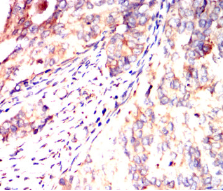

IHC    1/200 - 1/1000